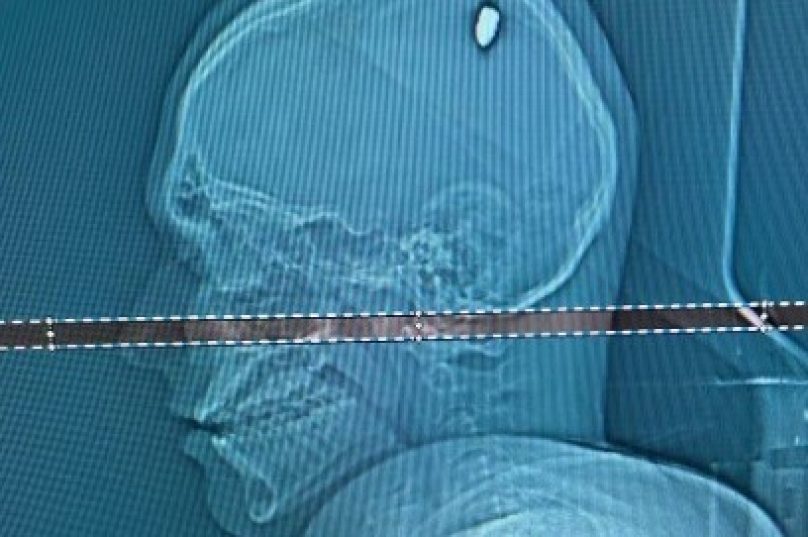

Exames realizados em um hospital particular de Juiz de Fora revelaram a presença de uma bala de calibre 9 milímetros alojada na cabeça de Mateus. A cirurgia para a remoção do projétil durou cerca de duas horas, seguida por dois dias na CTI e um no quarto, antes de receber alta.